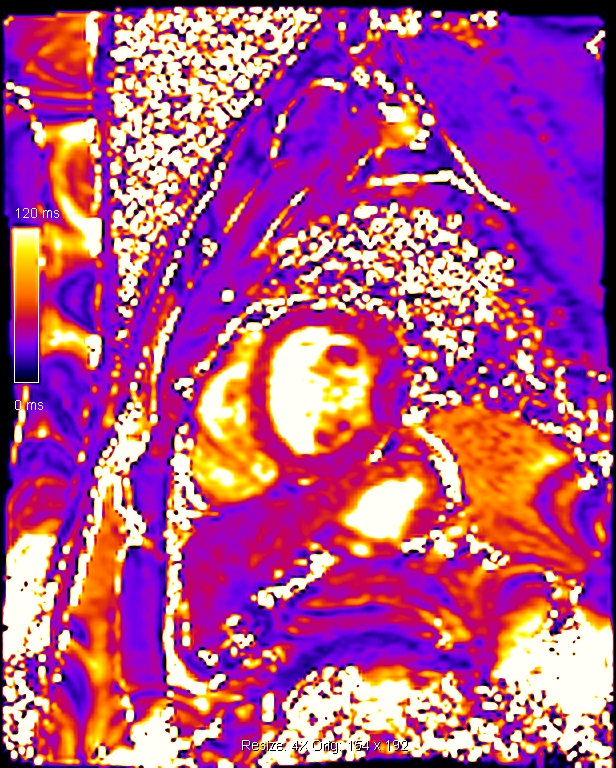

Η χαρτογράφηση του μυοκαρδίου με Τ1 και Τ2 ακολουθίες βοηθά στον γρήγορο, χωρίς τη χρήση σκιαγραφικού παράγοντα και ασφαλή χαρακτηρισμό του μυοκαρδίου και ανιχνεύει περιοχές με μυοκαρδιακό οίδημα και μυοκαρδιακή βλάβη όπως η ίνωση. Γίνεται συμπληρωματικά των κλασικών ακολουθιών της μαγνητικής τομογραφίας καρδιάς και προσφέρει πρόσθετες πληροφορίες για τυχόν βλάβες στο μυοκάρδιο ειδικά σε εξετάσεις όπου υπάρχει αντένδειξη στη χορήγηση ενδοφλέβιου σκιαγραφικού όπως είναι η κύηση ή προϋπάρχουσα αλλεργία (εικόνες 3,4).

Εικόνα 2. Μαγνητική τομογραφία καρδιάς με χαρτογράφηση του μυοκαρδίου: